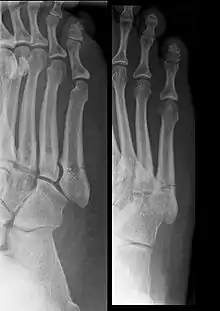

كسر جونز (بالإنجليزية: Jones fracture) هو كسر يصيب قاعدة المشطية الخامسة للقدم، وهي المشطية الواقعة عند قاعدة إصبع القدم الأصغر. ويشكو المصاب بهذا الكسر من ألم وتورم بهذه المنطقة مع صعوبة في المشي.

يظهر الكسر أقصى يمين الأشعة في قاعدة المشطية الخامسة